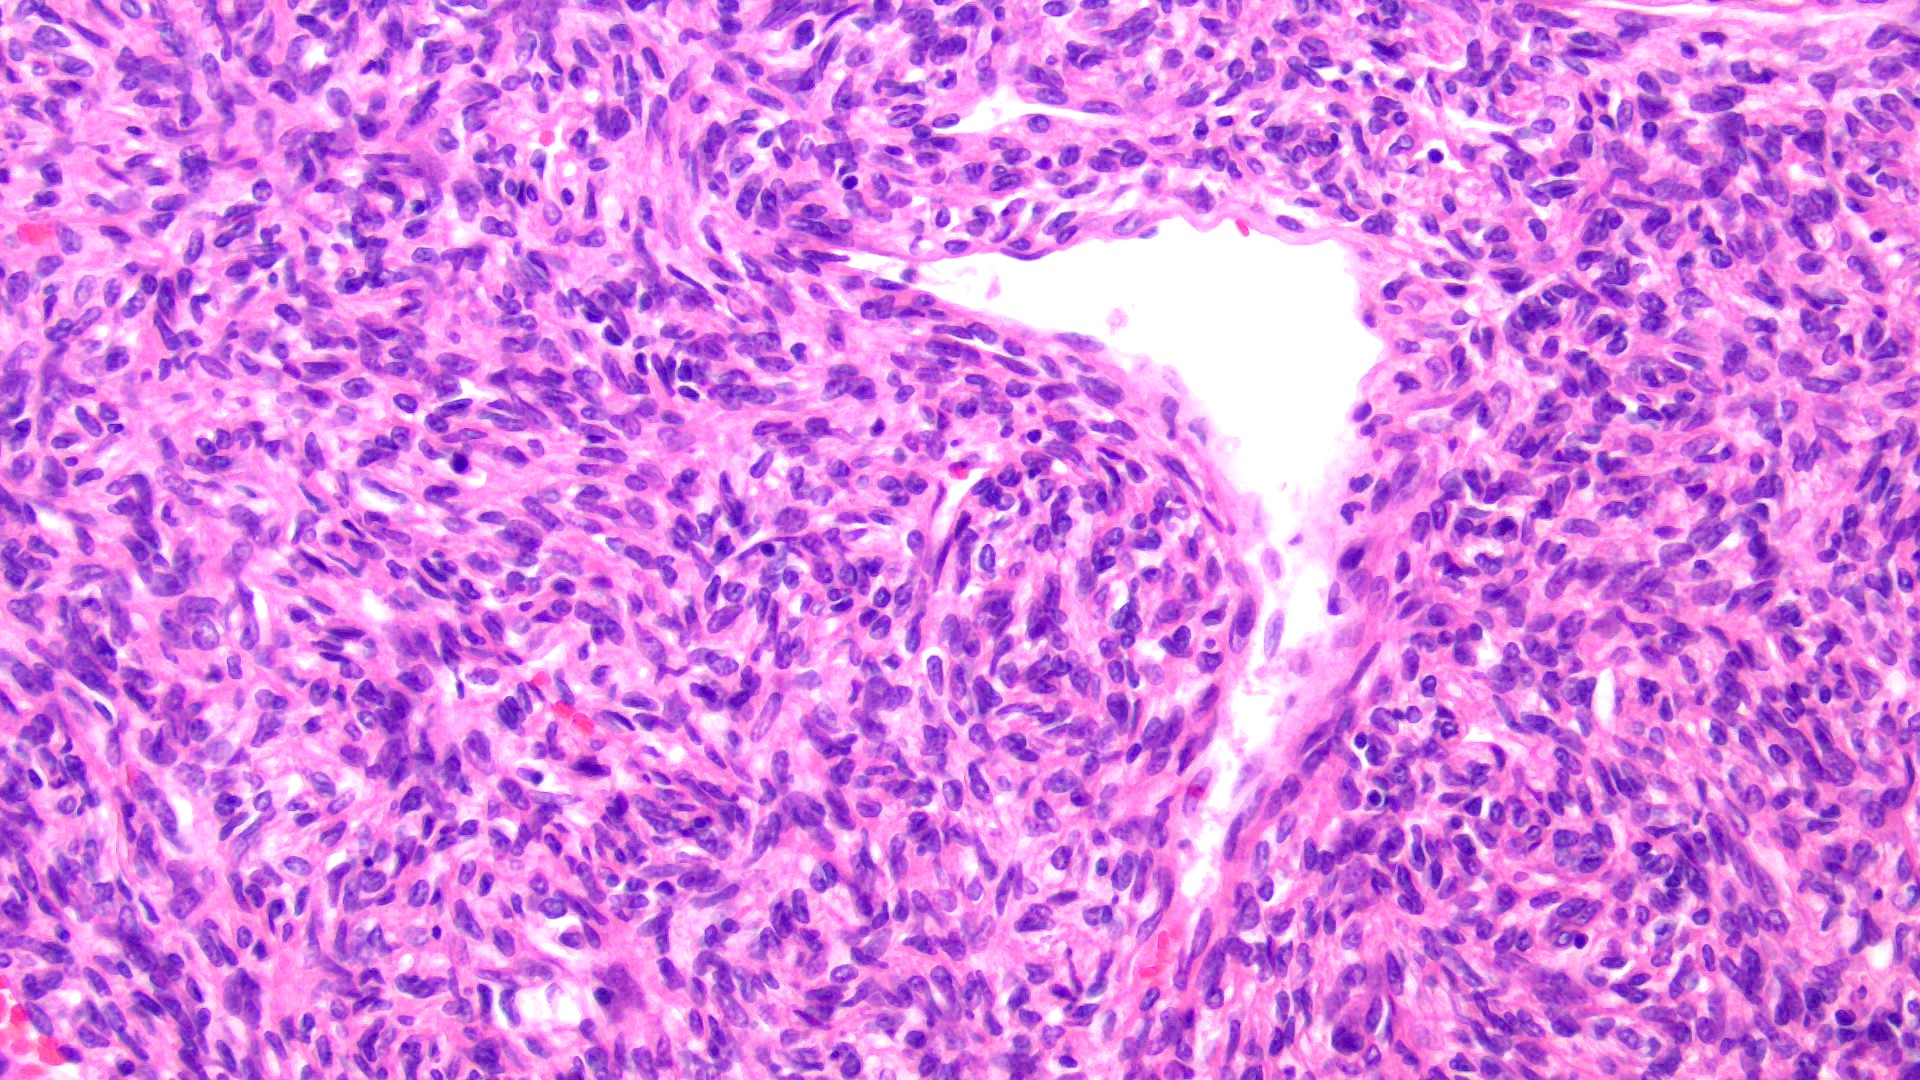

42-year-old male with hypoglycemia, altered mental status, and large skull-based mass with prominent veins. Diagnosis and genetics? (H&E and CD34)

Answer: B: Hemangiopericytoma / NAB2-STAT6 fusion